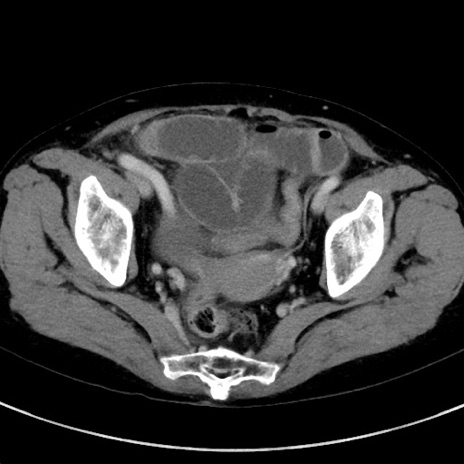

症例23(横断像)

【症例】70歳代女性

【主訴】下腹部痛・嘔吐

【現病歴】2日前より腹痛あり。昨日嘔吐あり。症状改善しないため来院。

【既往歴】胃GISTに対して胃部分切除後。

【身体所見】BT 37.1℃、BP 128/77mmHg、腹部:平坦・軟、下腹部に圧痛あり。

【データ】WBC 10200、CRP 0.31